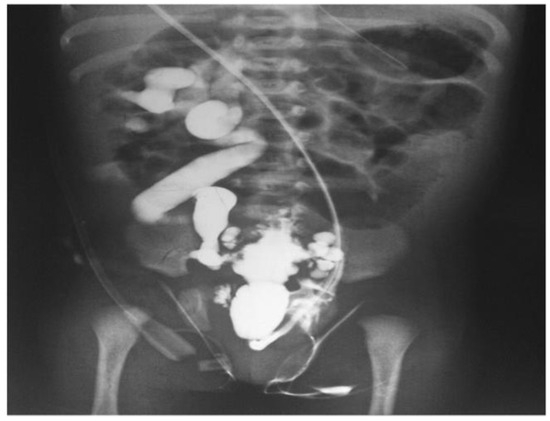

- Imaging modalities: A number of imaging modalities, such as intravenous pyelography (IVP), CT, MRI, and ultrasound, are essential for the diagnosis of juvenile kidney cancers and stones. Ultrasound is noninvasive and emits no ionizing radiation, so this method is used as a first-line imaging modality to examine renal morphology and identify structural problems (Figure 6). CT and MRI are more sensitive and specific for assessing stone load and identifying renal masses but also entail radiation exposure and require patient sedation [40].

- Treatment options: Tumor type, size, and location, and patient age are among the characteristics that influence how juvenile kidney tumors and stones are managed. Options for treatment vary from minimally invasive techniques and surgical intervention to cautious maintenance and attentive waiting. The primary therapy for kidney cancers that are localized is surgical excision; nephron-sparing techniques are recommended whenever possible in order to maintain renal function. Alternatively, depending on the size and composition of the stones, medicinal therapy, dietary changes, and minimally invasive techniques like ureteroscopy or shock wave lithotripsy (SWL) may be employed [41].